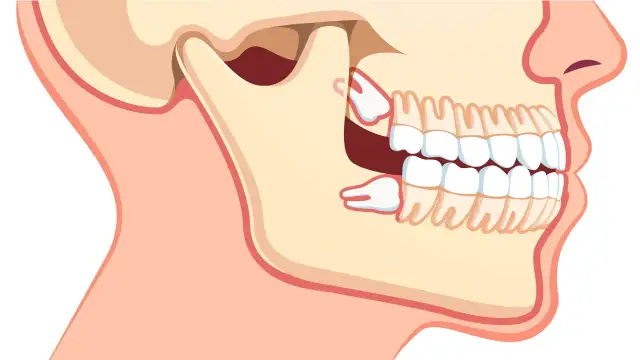

Wyrzynanie zęba stałego - ile trwa i kiedy do dentysty?

Wyrzynanie zęba stałego - ile trwa? Poznaj etapy, widełki wiekowe i dowiedz się, kiedy opóźnienie wymaga wizyty u stomatologa dziecięcego. Sprawdź!